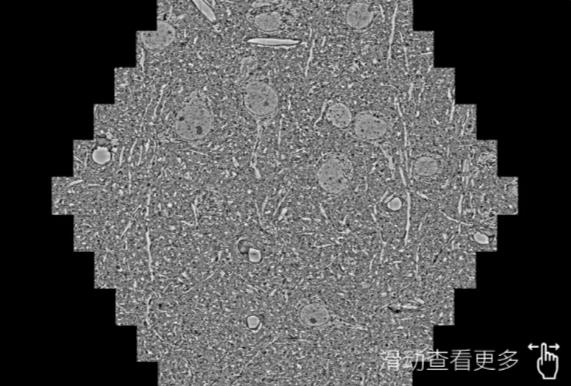

鼠脑切片。左图使用固原蔡司固原扫描电镜MultiSEM706对165μmx143pm面积区域成像,耗时仅需1.5秒。右图为鼠脑切片中30μm区域放大效果。样品由芝加哥大学B.Kasthuri提供。

使用蔡司高速固原扫描电镜MultiSEM对1mm²人脑皮层组织进行高分辨成像,并对其中的各种细胞结构进行三维重构分析。左图展示了2x3mm²组织平面中锥体神经元的三维重构效果。右图显示了局部体积神经元三维重构。图像由哈佛大学chtman实验室提供,渲染图由D. Berger 制作。